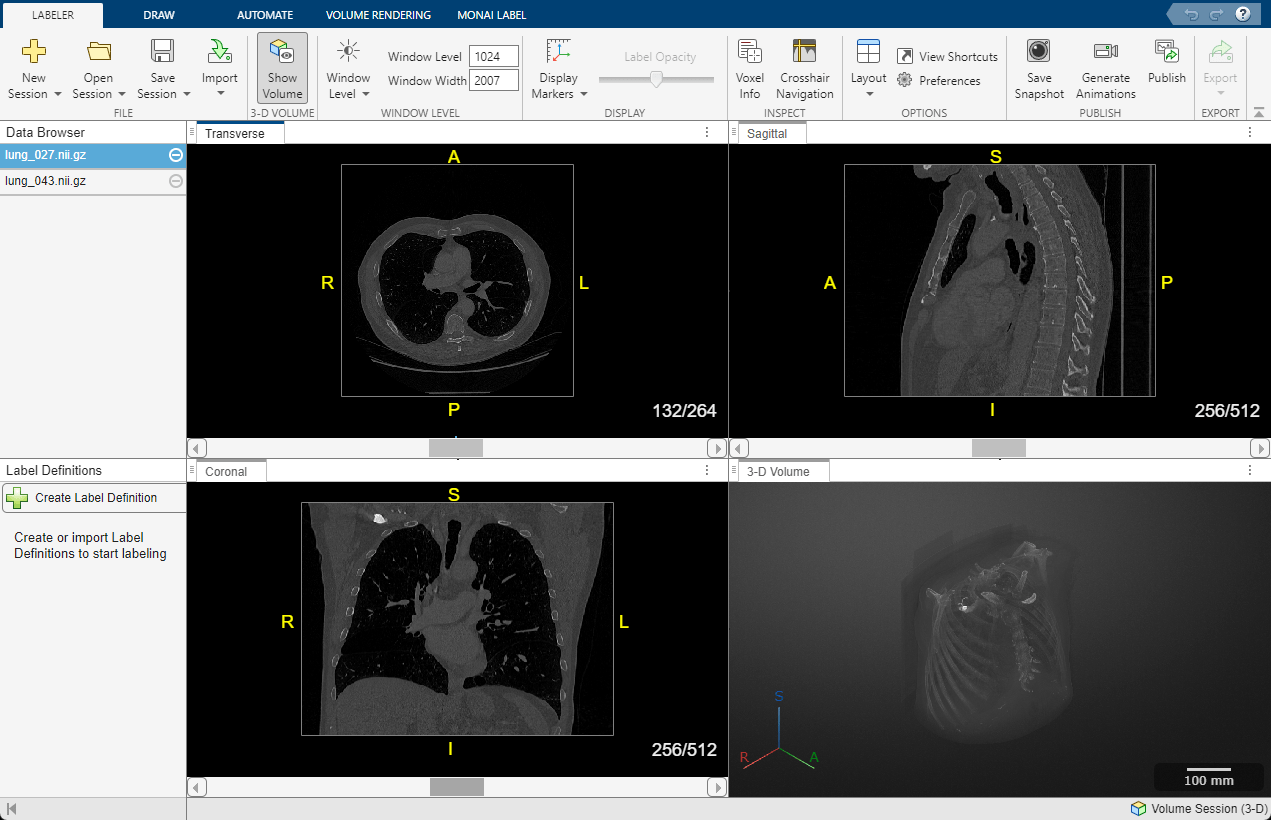

Screenshot showing transverse, sagittal, coronal, and 3-D volume DICOM images of a chest CT scan with labels.

3D chest CT scan in DICOM format visualized using Medical Image Labeler in Medical Imaging Toolbox. (See documentation.